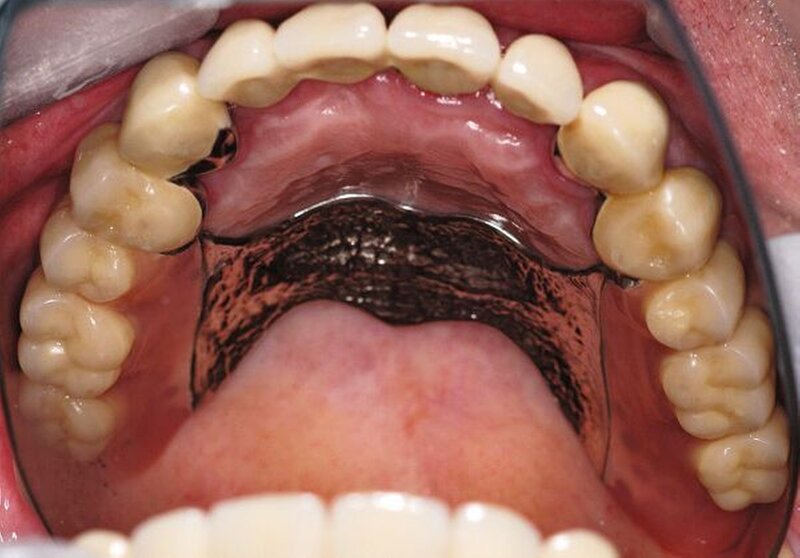

In der darauf folgenden Sitzung wurden alle Kronen und Brücken sowie die teleskopgetragene, partielle obere Prothese für einen Zeitraum von sieben Tagen zum Probetragen mittels eines Zements auf Zinkoxid-Eugenol-Basis eingegliedert. Dem Patienten sollte durch das Probetragen der Restaurationen beziehungsweise des angefertigten Zahnersatzes die Möglichkeit gegeben werden, sowohl die Funktion beim Essen und Sprechen als auch die Ästhetik im sozialen Umfeld zu testen. Ein erneutes Entnehmen der Restaurationen wäre – für den Fall notwendiger Korrekturen – somit ohne Weiteres möglich gewesen. Da der Patient sowohl die Funktion als auch die Ästhetik betreffend keine Änderungswünsche vorbrachte und auch keine neuerlichen Beschwerden aufgetreten waren, konnten die Restaurationen nach besagtem Tragezeitraum von sieben Tagen entnommen, gesäubert und mittels eines Glasionomerzements definitiv befestigt werden. Im Anschluss wurden erneut Situationsabformungen der Kiefer genommen und der Patient erhielt nach erneutem Checkbiss-Registrat, eine okklusal adjustierte Stabilisierungsschiene im Unterkiefer. Diese dient der Therapie der beschriebenen Bruxismusproblematik und gewährleistet einen langfristen Erfolg der eingegliederten prothetischen Restaurationen (Abbildungen 13a, 13b, 13c, 14, 15a, 15b, 15c).

Abschließend kann somit festgehalten werden, dass durch die gewählte Restaurationsform sowie durch die Art der technischen Umsetzung ein funktionell und ästhetisch sehr gutes Ergebnis erreicht werden konnte. Die Prognose des angefertigten Zahnersatzes ist bei entsprechender Compliance des Patienten sowie aufgrund der guten werkstofftechnischen Eigenschaften über einen Zeitraum von vielen Jahren als sehr gut einzustufen (Abbildungen 16a, 16b, 16c, 16d, 16e ).